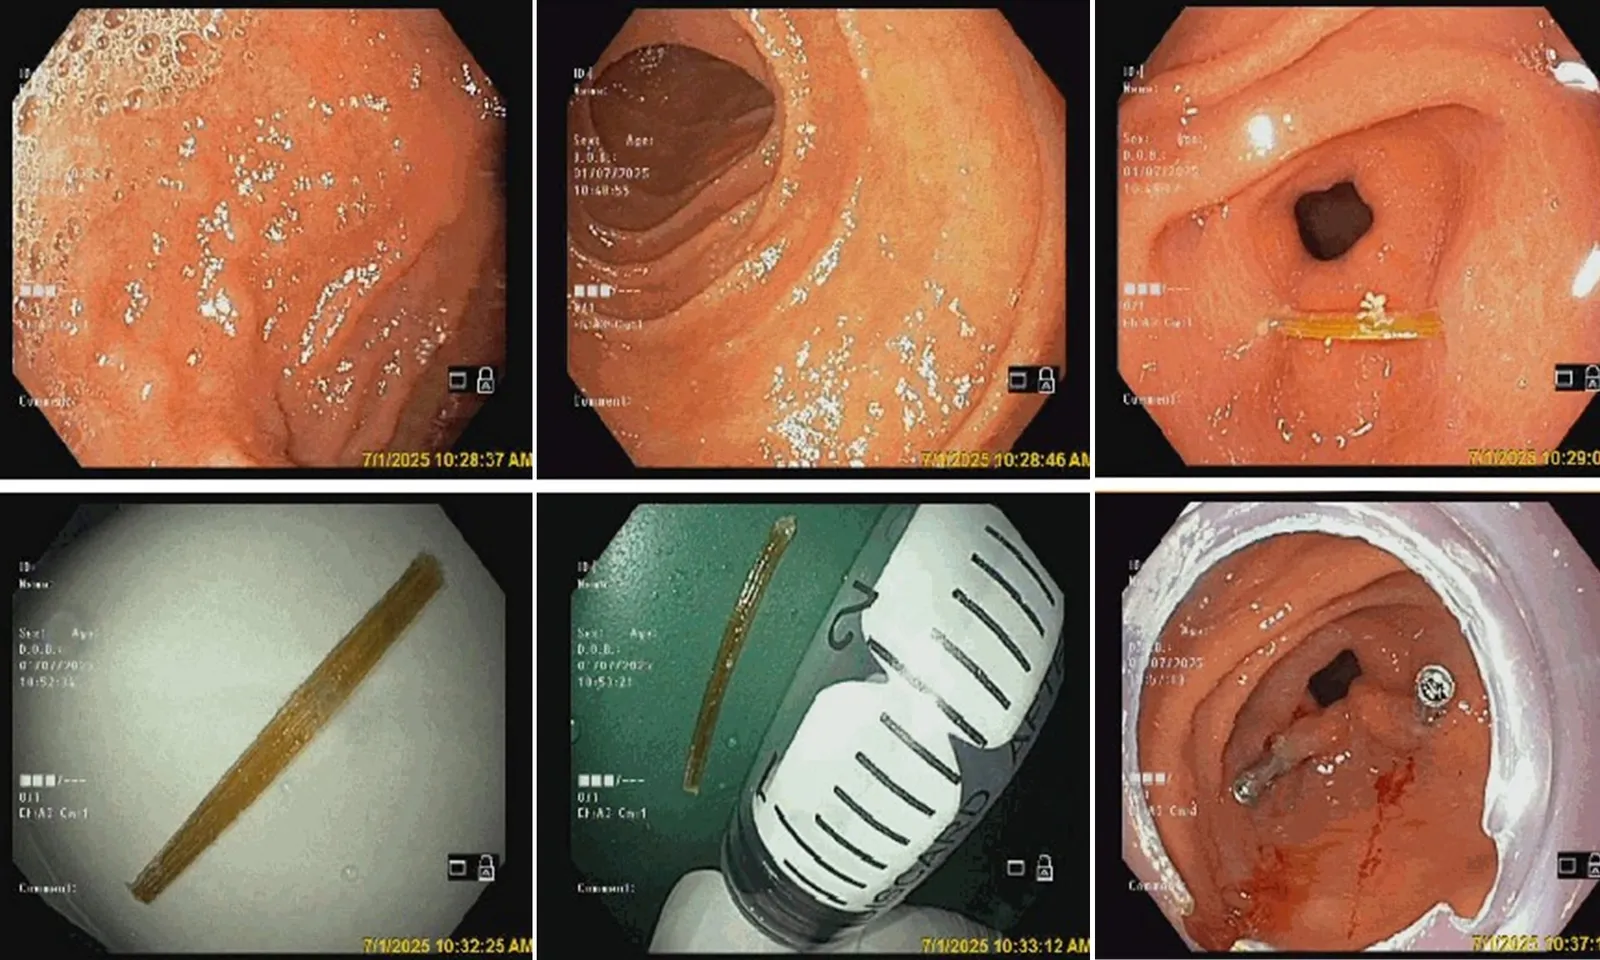

Bệnh nhân được chỉ định phẫu thuật lấy dị vật. Trong quá trình phẫu thuật, các bác sĩ lấy ra đoạn xương cá sắc nhọn dài khoảng 3cm. Đây cũng chính là nguyên nhân gây thủng ruột của bệnh nhân.

Kết quả chẩn đoán hình ảnh cho thấy có dị vật sắc nhọn xuyên thành ruột. Bệnh nhân được chỉ định phẫu thuật lấy dị vật. Sau phẫu thuật, các bác sĩ lấy ra một chiếc tăm tre dài gần 3cm.

Ngoài 2 ca bệnh trên, Bệnh viện Đa khoa tỉnh Phú Thọ đã nhiều lần thực hiện phẫu thuật lấy các dị vật đường tiêu hóa mà bệnh nhân vô tình nuốt phải bao gồm: xương cá, xương gà, bã thức ăn lớn gây tắc ruột, răng giả, đinh ốc vít, sợi kim loại, viên thuốc chưa bóc vỏ… Trong đó, nhiều bệnh nhân nuốt tăm do có thói quen ngậm tăm sau khi ăn, ngậm tăm khi đi ngủ…